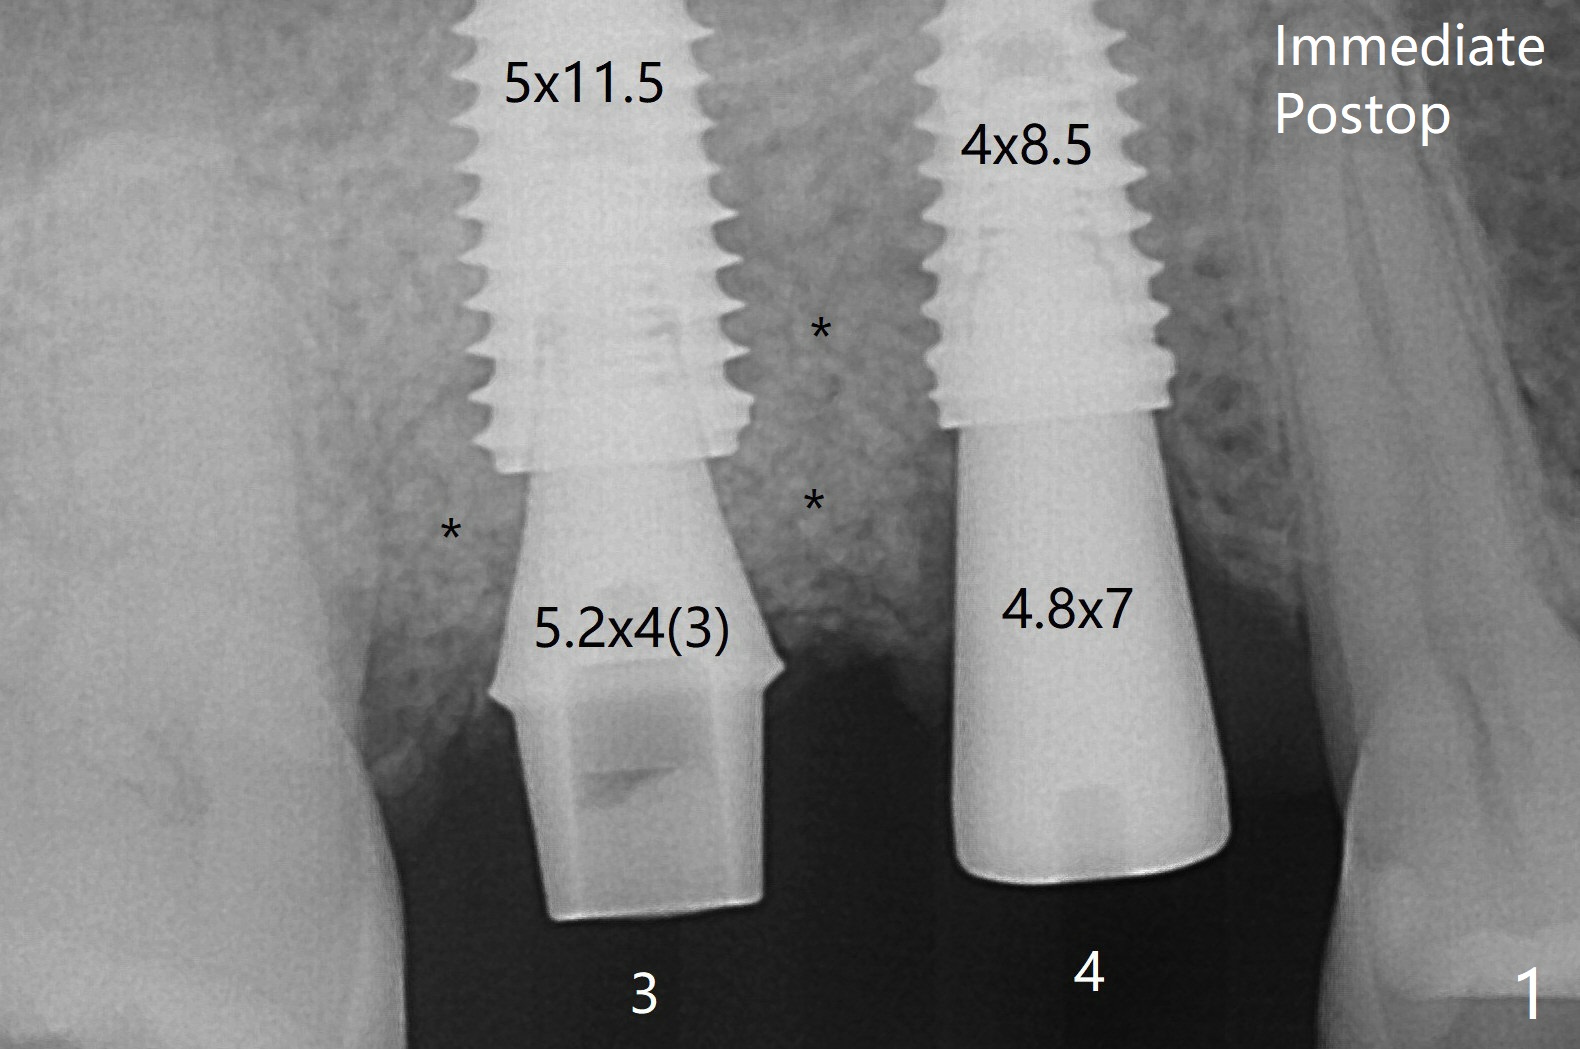

When the tooth #3 with severe buccal gingival recession is extracted and implants are placed at #3 and 4 with guide, sticky bone in 2 large pieces is packed between these implants with a previously large defect in a seemingly secure manner (Fig.1 *). Use of a longer implant at #3 (11.5 mm vs. 10 mm) will reduce the chance of abutment screw loosening in the future. The implant at #3 is placed in the palatal socket without apparently no sinus lift. Apparently new bone forms between the implants 4 months postop (Fig.5). The abutment at #3 may not be completely seated.